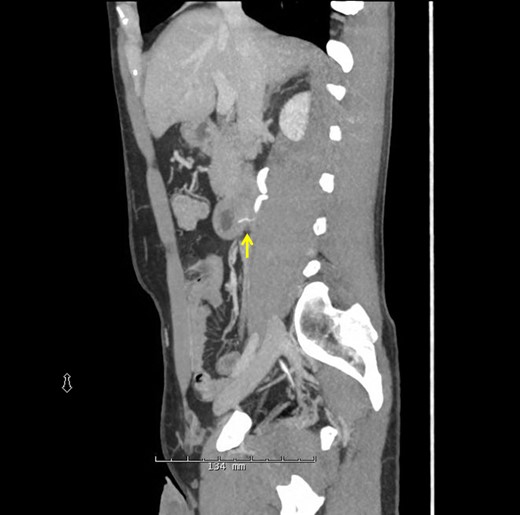

A 38-year-old male presented to the hospital with a chief complaint of abdominal pain and hematuria 1 day after eating a barbecue pulled pork sandwich. He described the pain as ‘deep’ in his abdomen, sharp and non-radiating with no episodes of nausea, emesis or diarrhea. He denied any dysuria or frequency. The patient's past medical and surgical history was unremarkable. He had no abnormalities on his laboratory values besides a urinalysis demonstrating 2+ blood and 11–24 RBCs/hpf. Physical examination revealed point tenderness to deep palpation to the right of his umbilicus, but his abdomen was soft with no signs of peritonitis. An upright abdominal X-ray was unremarkable; however, a CT of his abdomen demonstrated a 2-cm linear density representing the FB in the posterior third portion of the duodenum perforating into the retroperitoneum abutting the right ureter causing hydronephrosis (Figs 1 and 2, arrow). Two separate attempts were made at endoscopic retrieval in the first 24 h without successful visualization or removal of the FB. Due to the ureteral involvement and hydronephrosis, an operative intervention was recommended.

CT scan of linear opaque FB traversing the posterior wall of the duodenum abutting the ureter.